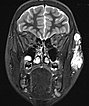

Axial, T2-weighted fat-suppressed MRI of the face. The venous malformation appears typically very hyperintense here too. No expansion into the depth.